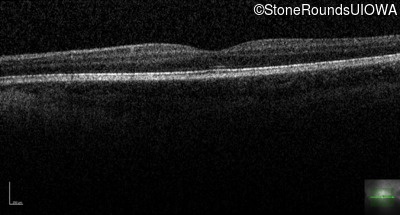

Congenital Stationary Synaptic Dysfunction (IA2g)

Age at visit:

10 years

OD

OS

20/63 -1 sc

20/80 -2